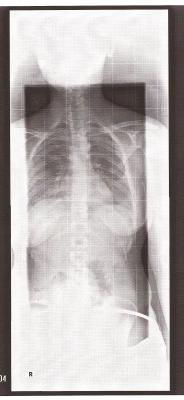

Nun zu dir: Ich gehe jetzt mal davon aus, dass eine Skoliose ausgeschlossen wurde?! Kommt denn diese Schiefheit dann von diesem Hüftproblem? Silas hat oben ja auch schon geschrieben, dass es nicht nach einer Skoliose aussieht, denn deine Wirbelsäule an sich ist ja gerade.

es tut mir leid, dass dein Besuch bei Dr. Hoffmann für dich nicht so gut lief. Aber wenigstens konnte eine Skoliose ausgeschlossen werden (und ich konnte auf deinem eingestellten Röbi auch keine erkennen), das ist doch schonmal gut.

Also einen Flachrücken sehe ich da nun wirklich nicht, eher einen ganz leichten Rundrücken und vor allen dingen das deutliche Hohlkreuz, was optisch wohl nicht so in den Vordergrund triit, im Gegensatz zu den Wirbelkörpern. Die HWS sieht man leider nicht, da könnte evtl. auch ein Anteil des Ausgleichs des Hohlkreuzes liegenlenaluna hat geschrieben:meine Orhtopädin diagnostizierte einen ausgeprägten Hohl-Rundrücken, der dringend Muskelaufbau braucht; Dr. C. aus Bochum diagnostizierte einen ausgeprägten Flachrücken, den ich bei novotergum behandeln lassen soll; Dr. H. aus Leonberg hat mir einen völlig gesunden Rücken diagnostiziert

Und die Aussage von Dr. Hoffmann über "völlig gesund" ist bezüglich der frontalen Aufnahme gemeint oder ?